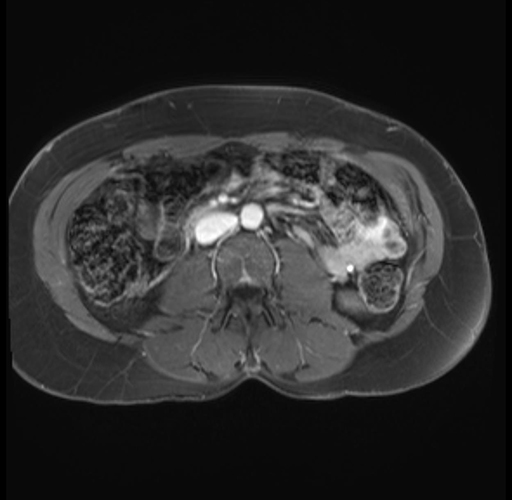

Laparoscopic distal pancreatectomy with possible splenectomy [case 14]

Imaging Analysis

Look through the patient's CT scan to identify any areas of concern for the necessary procedure.

Based on your CT findings, which issue(s) are present and would give reason for "planned slowing down moment(s)" in this case?

Considering a standard distal pancreatectomy procedure, what step(s) of the operation would you do differently in this case?